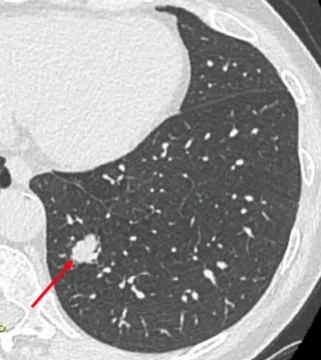

L’intelligence artificielle (IA) appliquée à l’imagerie thoracique dans le dépistage du cancer du poumon intervient à trois niveaux : i) l’aide à la détection de nodules, ii)la caractérisation de la probabilité de malignité du(es) nodule(s) détecté(s) et, iii) l’aide à la prédiction d’apparition du cancer.

Quinze pourcents des personnes qui font l’objet d’un dépistage du cancer du poumon se voient découvrir un nodule de nature indéterminée (NNI) sur le scanner de dépistage. Moins de 15% de ces NNI sont des cancers débutants. Devant un NNI deux attitudes sont proposées : simple surveillance radiologique (une stabilité oriente vers la nature non cancéreuse du NNI) ou abord diagnostique qui n’est pas aisé car il s’agit de toutes petites lésions situées en plein milieu du poumon. Une troisième attitude fait l’objet d’évaluation dans certains centres spécialisés c’est l’administration de traitement préventifs, encore appelée interception du cancer. Nous envisageons de combiner les deux dernières stratégies grâce aux possibilités de l’endoscopie robotisée qui permet la caractérisation histopathologique, immunologique et moléculaire de lésions inaccessibles par les techniques diagnostiques usuelles.